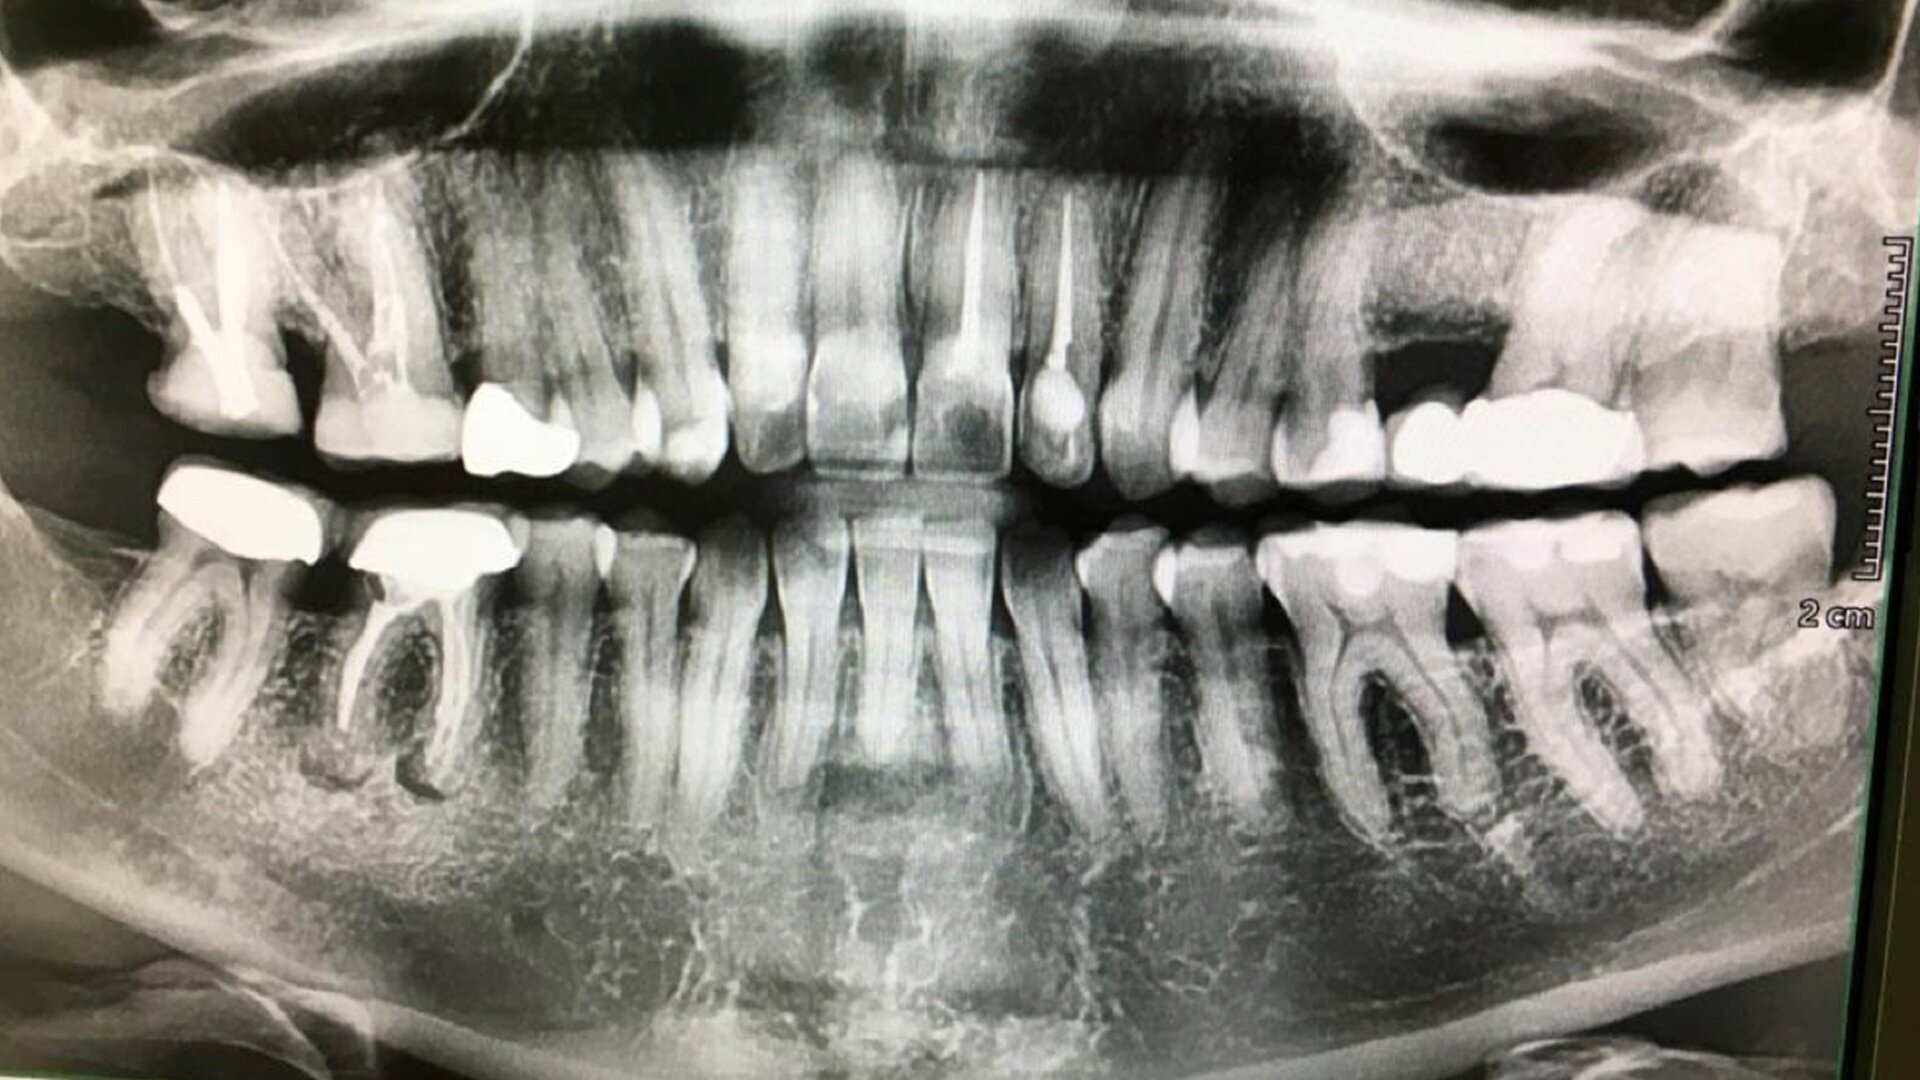

In this second case, the patient was referred by his general dentist for retreatment of his molar owing to pain on chewing (Fig. 10). On the medical file, treatment for melanoma was noted. Further questioning determined that he was taking bisphosphonate, among other medications. At this point, a CBCT scan was taken, and on it, we could see the quality of the bone clearly, including sequestra, typical of bisphosphonate-associated bone lesions (Figs. 11a–e). The reason for the occurrence in this area was the infection of the distal root due to a canal that had been missed during the root canal procedure. We consulted with the patient’s treating doctor, who recommended a long course of treatment with antibiotics for the interim and management of the necrotic bone that was showing under the tooth from the lingual side (Figs. 12a–d).

Figs. 13a & b: Panoramic and periapical follow-up images showing a radiolucency under the mandibular right first molar.

The patient in this case was referred back to check on a retreatment performed some years before. It was clear from the radiographs that the periapical area of the molar was not healthy (Figs. 13a & b). A CBCT scan was taken and, when studied in DTX software, showed a lesion under the molar (Figs. 14a–d). After a careful study of the case, it was determined that the lesion was unrelated to the apices, the periodontal ligament was not interrupted and the lesion had no clear epithelial lining. In order to establish the aetiology, the patient was asked about pain on chewing, but reported no discomfort whatsoever. He had also not been involved in a fight, but recalled having slipped when taking a shower and having hit his mandible on the bathtub.